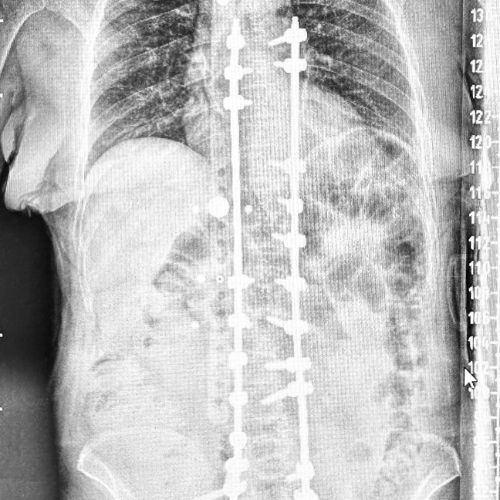

Escoliosis degenerativa del adulto

Curvatura lateral anormal de la columna por desgaste discal y articular. Genera dolor crónico, desequilibrio postural, limitación funcional, compresión nerviosa y deformidad progresiva en personas adultas.

Cirugía Robótica

La tecnología robótica se aplica cada vez más a las técnicas de cirugía mínimamente invasiva de la columna vertebral (MISS).